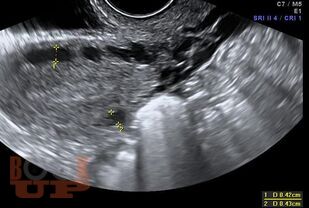

В пособии изложены современные принципы диагностики варикозной болезни вен таза. Представлена анатомия вен малого таза, этиопатогенез, классификация этого заболевания. Приводятся рекомендации о методологии инструментального исследования при этой патологии. Методические рекомендации предназначены для системы последипломного образования.